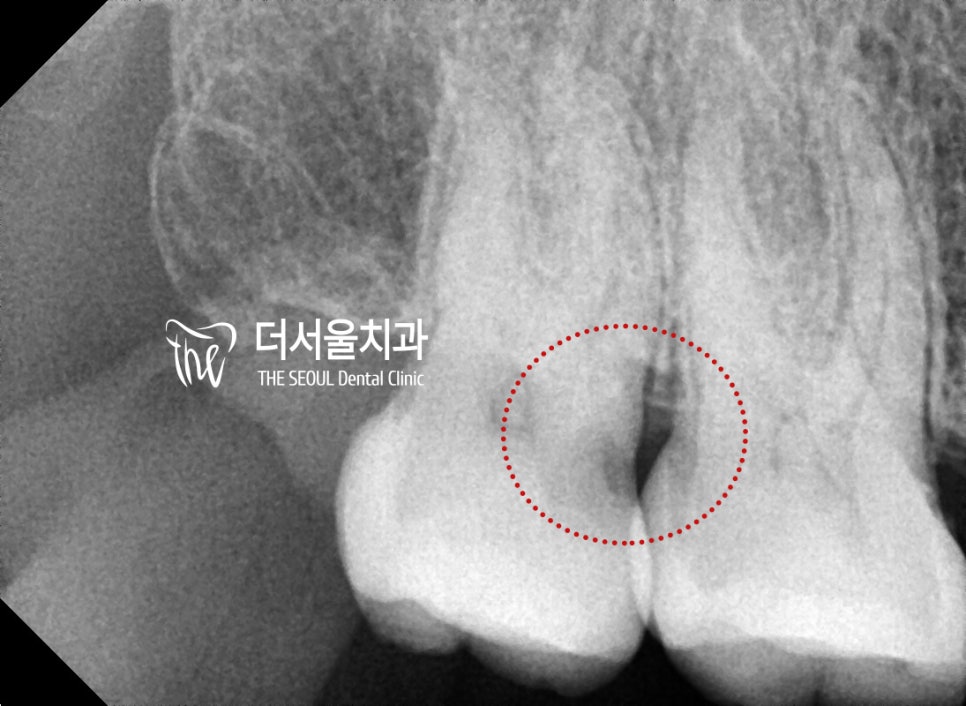

환자 분의 경우 치수강 근처

꽤 깊은 곳까지 우식이 퍼져 있었는데요

이런 경우에는 신경치료를 통해

썩어있는 곳을 제거한 뒤

새롭게 채워넣어야 됩니다.

# 17 어금니 신경치료를 시작하기로 했습니다.

특히 이곳은 맨 뒤쪽에 위치한 최후방구치라

기구 접근도 쉽지 않은 곳인데요.